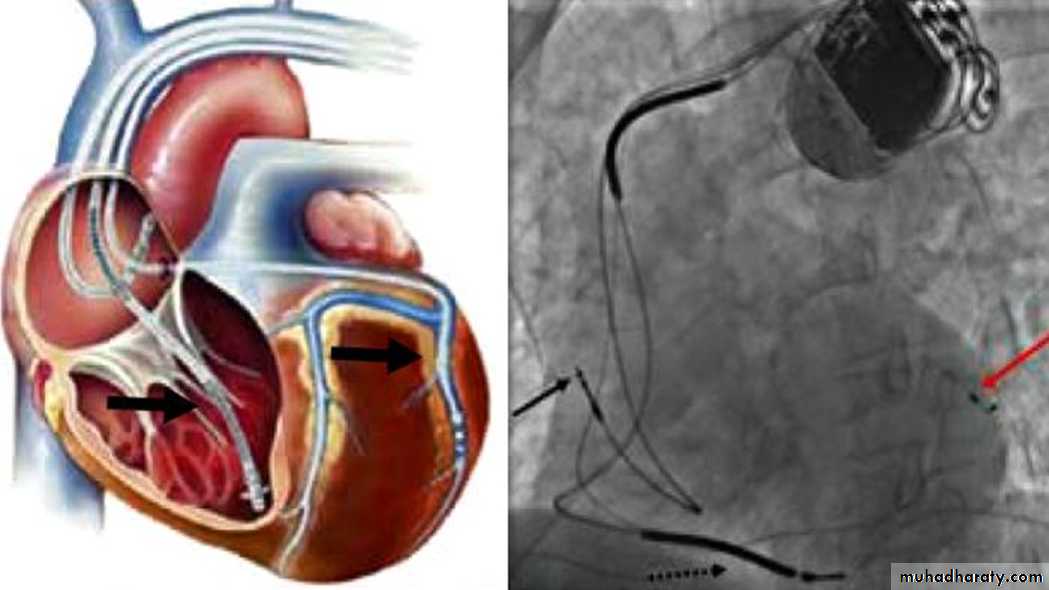

Implantable Cardioverter-Defibrillators for HF( ICD) –CRT

Sustained ventricular tachycardia is associated with sudden cardiac death in HF.

About one-third of mortality in HF is due to sudden cardiac death.Patients with ischemic or nonischemic cardiomyopathy, NYHA class II to III HF, and LVEF ≤ 35% have a significant survival benefit from an implantable cardioverter-defibrillator (ICD) for the primary prevention of SCD.

Cardiac-Resynchronization-Therapy